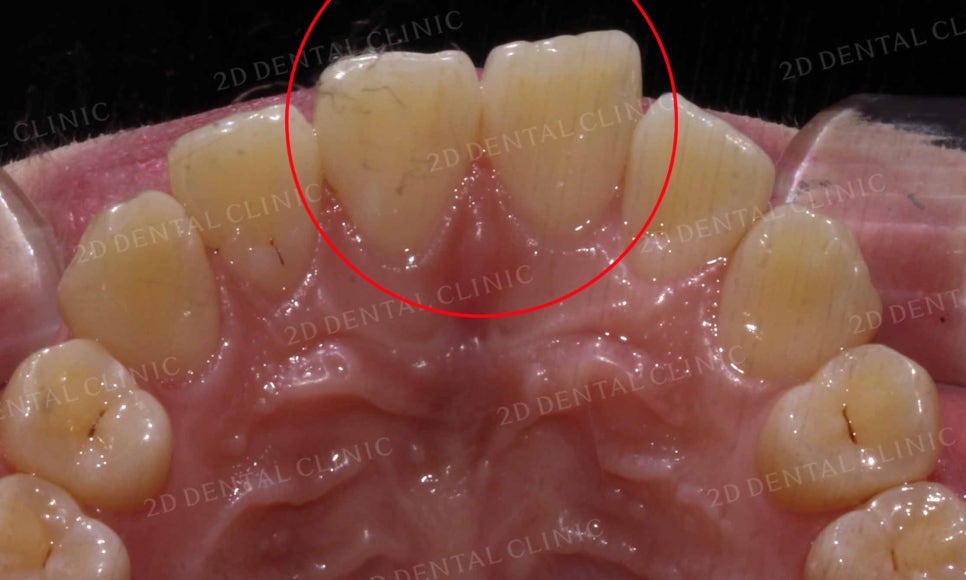

윗니의 치열을 보시면 앞니가

주변 치아들보다 바깥으로 뻗어져 있고

틀어짐도 심한 모습인데요,

흔히 토끼앞니 증상이 있으신 환자분들께서

앞니가 유난히 크다는 말씀을 하십니다.

그러나 이러한 치아의 크기차이는 치열이

흐트러짐으로 인해 발생하는 착시효과로

교정 후 정상적인 치열로 바뀌면

치아의 크기가 일정하게 보이게 됩니다.